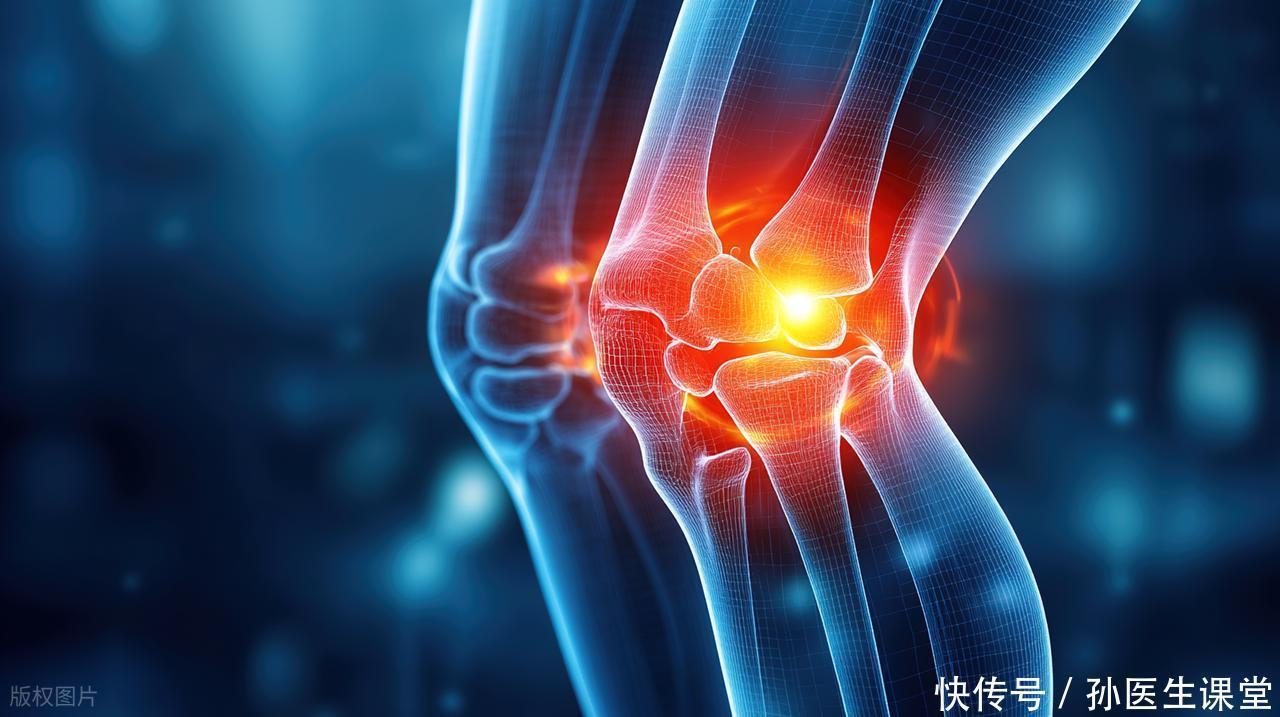

早期的感觉往往很轻:深部的髋部酸胀、走几步路后隐痛、久坐后站起的僵硬感,常被当作“腰腿痛”“肌肉劳损”。逐渐发展时,疼痛会从髋部放射到腹股沟、大腿前外侧或膝内侧,爬楼、蹲起困难,步态出现轻度跛行。到了后期,股骨头形态改变,关节间隙受累,疼痛从“偶尔不舒服”变成“持续影响睡眠”,这时再去就医,选择往往更被动。

需要特别提醒的是:出现以下信号时,请尽早就医评估——髋部或腹股沟深部疼痛持续超过数周;从坐到站需要慢慢“缓一缓”;走路开始出现不对称的摆动或者小步快走仍难以缓解疼痛;夜间痛影响睡眠且对常规止痛反应差。越早识别,越可能把握保守或关节保留治疗的窗口期。